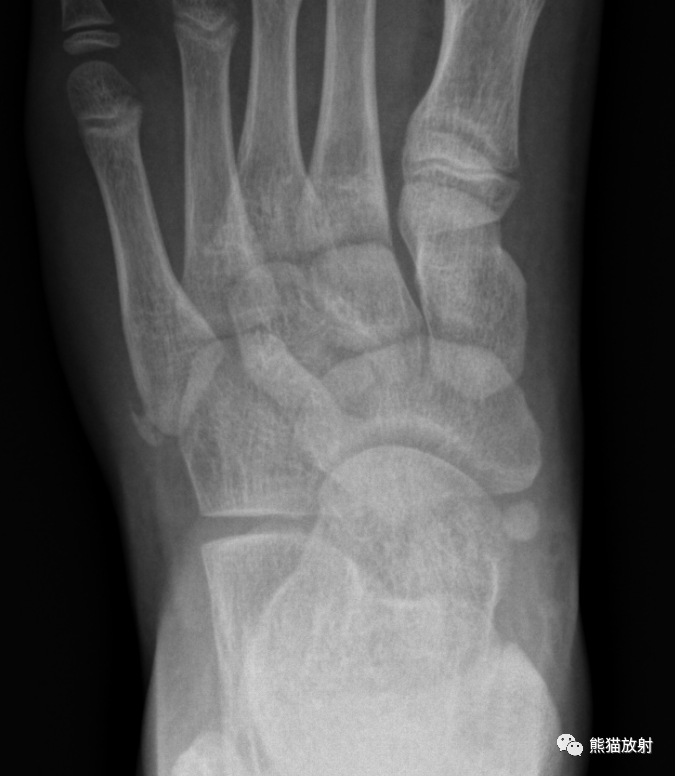

沿第五跖骨基底部长轴方向走行透亮影,骨折线多为横行

图片尺寸640x644